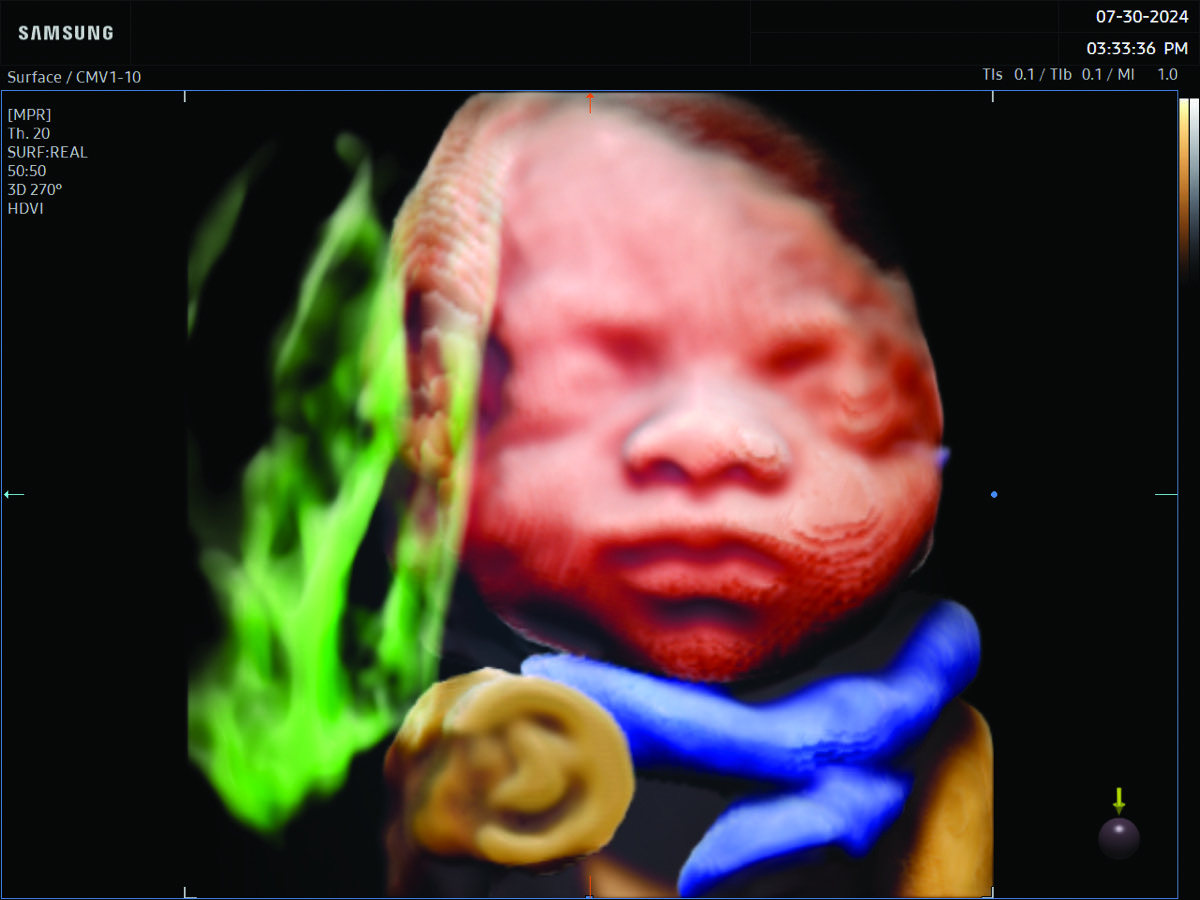

Comprehensive, advanced and expert MFM care for high-risk pregnancies

- Fetal anomalies